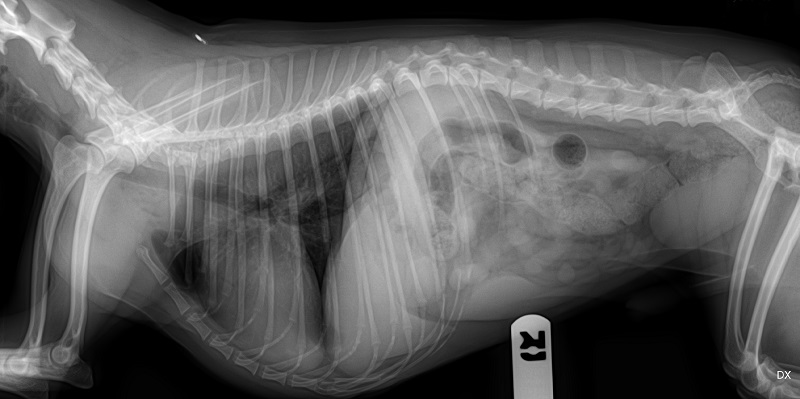

Para que os nossos pacientes beneficiem do melhor serviço possível, a Vethelp coloca ao seu dispor um aparelho de RX de alta frequência, que permite obter radiografias de qualidade em pacientes de qualquer dimensão e um Ecógrafo Doppler fixo, equipado com sondas que permitem realizar ecografias abdominais e ecocardiografias. Sendo que um exame não substitui o outro, pretendemos que ambos se completem, com o objetivo de elevar a qualidade e precisão diagnósticas.